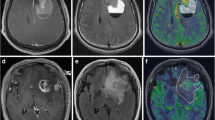

Data analysis was performed independently by two neuroradiologists and blinded to the histopathological and genetic/molecular characteristics. Tumor outlining and processing of ADC and rCBV maps were performed using nordicICE (NordicNeuroLab AS, Bergen, Norway). A series of ROIs were manually drawn on every representative slice for the entire tumor volume separately on ADC maps and T2-weighted images (Fig. 2). The borders were drawn at the transition between abnormal hyperintensity and normal parenchymal signal intensity based on visual evaluation with preferably avoidance of cystic components. The entire tumor volume includes both enhanced and non-enhanced components [23, 24]. Discrepancies were resolved by consensus reading.

Generation of rCBV and ADC histograms. Regions with signal hyperintensities were segmented on axial T2 images, coregistrated with rCBV maps and corresponding rCBV histogram in a 44-year-old woman with anaplastic oligodendroglioma (a, b). Total tumor volume was segmented on ADC maps in the same patient with corresponding ADC histogram (c, d)

Standard tracer kinetic models were used for creating CBV maps from DSC-MRI, corrected for potential contrast agent leakage from blood-brain barrier breakdown and normalized with respect to blood volume values from normal-appearing tissue to obtain relative CBV [24]. ADC maps from DWI were created using standard Stejskal-Tanner diffusion approximation [17, 25]. Whole-tumor normalized histogram distributions of the ADC and rCBV maps were created as described elsewhere [24]. In short, using MATLAB 2013 (MathWorks, Natick, Mass), 100 bin histograms were created over an ADC range of 0–300 and an rCBV range of 0–7.5 (ratios; arbitrary units), respectively. The histograms were normalized by making all areas under the curves equal to one to correct for varying tumor sizes [23]. To reduce the effect of outliers, all ADC and rCBV values below the 5% percentile and over the 95% percentile were excluded. The maximum peak heights of the normalized histogram (ADCPeak and rCBVPeak), as well as means of the tumor regions of interests (ADCMean, rCBVMean), were calculated. rCBVPeak and ADCPeak were statistically used as measures of vascular and cellular tumor heterogeneity, respectively [17, 23].